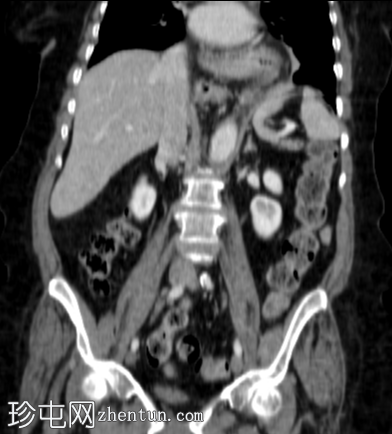

冠状C+门静脉期

胃食管连接处及大部分胃已疝入胸腔。

胃沿其长轴旋转。

无胃扩张或壁异常强化征象。

检查结果提示胃扭转疝入裂孔,无急性梗阻征象(不完全性)。